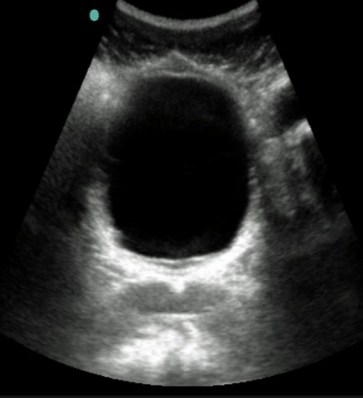

Para realizar este examen siempre será necesario que la vejiga esté llena, pues si está vacía la mayoría de órganos del abdomen impedirán que se visualice la próstata.

Tener la vejiga llena tiene dos funciones, 1. el líquido va a desplazar los otros órganos y, 2. la orina servirá como una «ventana» que permita ver la próstata con mayor precisión.

Cuando la vejiga esta vacía o con poco líquido no se puede apreciar la próstata tan bien como cuando esta medio llena. Tener la vejiga muy llena también puede dificultar la visión de la próstata.